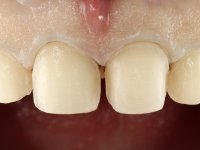

Realizado o diagnóstico e tomada a decisão quanto ao tratamento a executar, tornou-se importante definir qual a sequência de trabalho a adotar no sentido de conseguir a reabilitação da D.V.O. (V.D.O), de forma progressiva e equilibrada. Na primeira fase fez-se uma pré-impressão da arcada inferior com silicone tipo “putty” e em seguida realizou-se o preparo dentário de todo o sector posterior. O preparo para os overlays foi feito coronalmente à linha amelo cementaria no sentido de ser o mais conservador possível. A impressão foi feita com técnica de dupla mistura após afastamento gengival realizado com pasta de caulino. A provisória foi realizada com resina composta de polimerização dual. Em laboratório foram realizados os overlays após se ter aberto ligeiramente (1,5mm) a D.V.O. nos modelos montados em articulador semi-ajustável. Simultaneamente o sector antero-inferior foi encerado no sentido de acompanhar este aumento da D.V.O. Também foi confecionada uma chave de silicone translucido para posterior confeção dos provisórios antero-inferiores. Em boca foi primeiro realizada a provisionalização dos dentes anteriores utilizando resina composta previamente aquecida após preparação das superfícies dentárias para a adesão. Foi colocado o dique de borracha para promover o isolamento absoluto e posteriormente foram colados os overlays. Em laboratório foi realizada nova chave de silicone para confecionar os provisórios antero-superiores. Seguidamente em boca foram preparados os seis dentes antero-superiores após colocação do fio de afastamento gengival. Feita a preparação adequada das superfícies dentárias foi realizada a impressão com técnica de dupla mistura e a respetiva provisória. Em laboratório foram confecionadas 6 facetas feldespáticas num modelo de trabalho tipo “Geller”. A provisória foi removida e as facetas foram coladas em boca utilizando um isolamento relativo competente. Esta opção foi tomada em virtude de uma prévia experiencia negativa com a colocação do dique de borracha na mandibula. Após a colagem dos laminados antero-superiores foram dadas 12 semanas para avaliar a adaptação do paciente à nova situação e então iniciar a confeção das facetas antero-inferiores. Após colocação do fio de afastamento gengival. foram feitos os preparos dentários adequados e em seguida foi feita a impressão. Também foi feita a preparação do dente 3.4 que, entretanto, tinha sofrido uma fratura do overlay. As facetas e a restauração do 3.4 foram realizadas num modelo de trabalho tipo “Geller”. Após remoção da provisória, as facetas foram coladas em boca, utilizando um isolamento relativo pelas razões apontadas anteriormente. Após colocação do trabalho o paciente foi reabilitado por outros colegas com um implante na zona do 2.6 e substituição da coroa aparafusada sobre o implante colocado no local do 3.5. Posteriormente surgiram fraturas nos overlays dos dentes 4.7 e 3.7 que foram reabilitados com overlays em Zr.